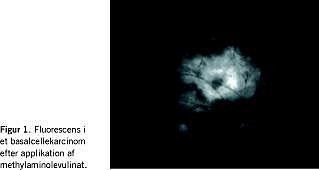

Basalcellekarcinom (BCC) og spinocellulært karcinom er de hyppigste maligne tumorer hos mennesker. I modsætning til traditionelle kirurgiske behandlinger (curettage, excision og frysning) baseres de nyere metoder på lokal immunstimulation og fotodynamisk effekt (PDT). Begge er veldokumenterede til behandling af BCC. Især PDT, hvor tumorceller sensibiliseres over for synligt lys ved hjælp af methylaminolevulinat (Figur 1 ), har vundet indpas til behandling af in situ-karcinomer og invasive karcinomer. Behandling med PDT har et fremragende kosmetisk resultat (ingen ar eller suturmærker) og gør det nemt at behandle multiple tumorer. Invasive karcinomer kan formentligt forebygges ved at fjerne in situ-læsioner, hvilket er specielt relevant hos immunsupprimerede patienter, hos hvem hyppigheden af hudkræft er høj, og metastaser er en reel trussel.